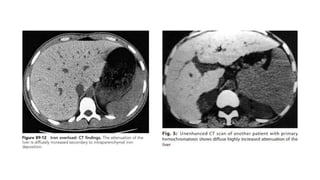

CT

• Normal liver density : 45 and 65 HU on NCCT

• In hemochromatosis liver shows homogeneously increased

density with an attenuation of greater than 72 HU .